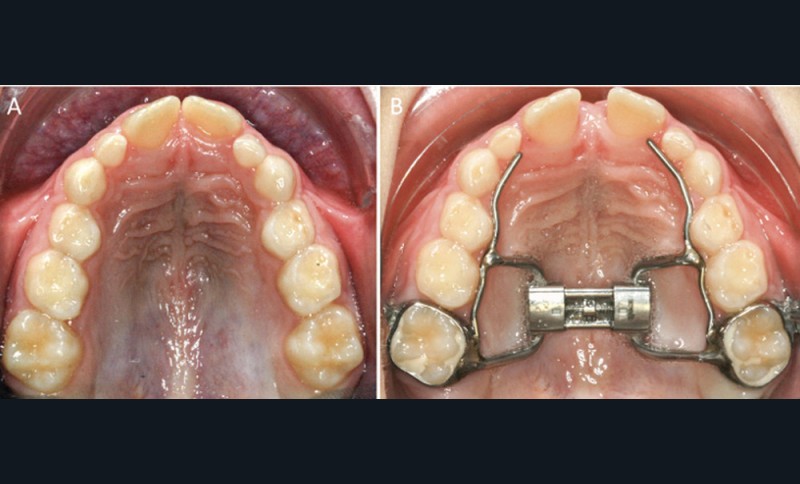

L’expansion maxillaire rapide

Les enfants apnéiques présentent souvent une insuffisance de croissance transversale du maxillaire. L’Expansion maxillaire rapide (EMR) chez les enfants en cours de croissance, par la disjonction de la suture médio-palatine, permet de corriger cette anomalie ainsi que l’encombrement dentaire associé (fig. 9). C’est une technique largement utilisée, bien acceptée par les patients et qui facilite la prise en charge ultérieure des autres anomalies orthodontiques, notamment de la dimension antéropostérieure.

C’est une thérapeutique de choix chez les enfants atteints de Sahos : elle améliorerait la qualité du sommeil à court et long terme par l’augmentation du volume des VAS (au niveau du palais et des fosses nasales) [25-26-27-28]. L’EMR, par l’élargissement du maxillaire, crée un espace suffisant pour la langue, favorisant sa position haute. Une ascension de l’os hyoïde, associée à ce changement de posture linguale après l’expansion maxillaire rapide, a été mise en évidence dans la littérature [27-29-30]. Au cours de la croissance, l’EMR pourrait s’inscrire dans un traitement orthodontique global qui vise à corriger également les sens antéropostérieur ou vertical. Enfin, et malgré son efficacité, cette thérapeutique peut ne pas traiter complètement certains patients chez qui les symptômes de Sahos ne s’améliorent pas (Villa, 2015, Guilleminault, 2011). Dans ce cas-là, des traitements orthodontico-chirurgicaux seront alors indiqués.